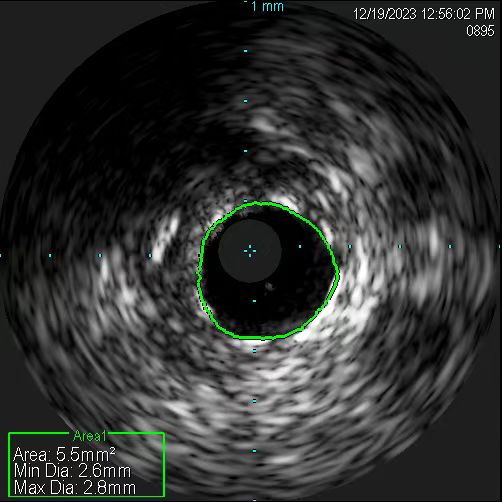

在无造影剂显影情况下,冠脉导丝能否送达病变血管远端,是手术的关键一步。操作稍有不慎,导丝就可能误入分支,也可能穿出血管,引发致命后果。患者及家属的充分信任,是手术得以进行的先决条件。12月19日11时许,在具备手术条件时,张慧晶带领手术小组成员开始了挑战。术前各项准备完成后,韩世飞在李占虎协助下将指引导管顺利放置于右冠开口,他依据丰富的手术经验,将导丝成功送入到右冠远端,血管内超声(IVUS)探头顺利到位后便开始进行精准的检查。结果提示:患者右冠原支架贴壁良好、膨胀充分,进一步证实了此次犯病不是源于右冠。再行前降支IVUS检查,依靠上次冠脉造影图像作为参照,指引导管、主支导丝顺利到位,反复多次进行IVUS检查。张宏博根据IVUS图像及时进行精准的测量,前降支近段最小管腔面积2.7mm2,中段斑块负荷重,均达到处理标准;远段血管直径约2.5mm,近段血管直径约3mm。张慧晶带领大家根据IVUS检查结果,制定了详尽的支架植入方案:应用血管内超声的换能器精准测量,辅以分支导丝做为路标,一举将支架成功释放到理想位置。最终经IVUS检查提示:支架膨胀充分、贴壁良好,无残余狭窄及边缘夹层。历时近2小时,手术过程顺利,全程未使用一滴造影剂,患者未出现任何不适及并发症。术后复查心脏超声较前无变化,无心包积液,确定了无穿孔发生。